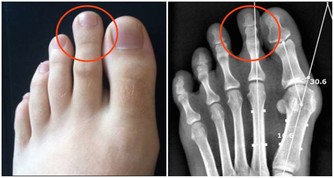

鞋底內側磨損較多

可能是兩腿的膝關節向外分離,導致小腿脛骨向內翻轉一定角度。嚴重的話會形成O形腿或「內八字」。如果邁著外八字腳步,說明腳趾向外的角度過大,時間久了,會讓膝蓋外移,雙腿變形。隨著年齡增長,可導致膝關節疼痛以及加速關節退化,甚至引起腰椎不適。

4、鞋底內側的磨損較多

鞋底內側的磨損較多,俗稱內八字,腳板過度內翻或是先天性的扁平足,膝關節向內側壓縮,易導致關節扭傷、損傷。

B.鞋跟內側都出現磨損

這種情況,是因為兩腿的膝關節向外分離、小腿脛骨向內翻轉了一定角度造成的。如果磨損十分嚴重,就意味著你的膝蓋已經外移,雙腿已經變形,變成「O形腿」或「內八字」。

隨著年齡增長,這種情況容易導致膝關節疼痛以及加速關節退化,甚至引起腰椎不適。